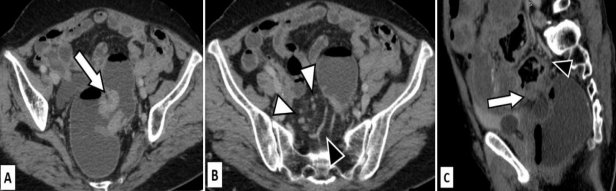

Figure 2: True positive for T3 and N positive disease.

A 65 years old female presented with PR bleed. Ultrasound done showed dilated small and large bowel loops.

Figures 2A (axial), 2B (coronal) and 2C (Sagittal) CT images in venous phase show telescoping of sigmoid colon into the rectum suggestive of intussusception (arrows). The pericolic fat appears normal, however an enhancing mass can be seen at the of the intussusception. Multiple sub centimetric lymph nodes are seen (arrowheads).

Figure 2D (magnified axial CT image in venous phase) shows cluster of nodes with perinodal stranding. One of the nodes shows heterogeneous enhancement (arrowhead).

T3, N positive disease was confirmed on post-operative histopathology.